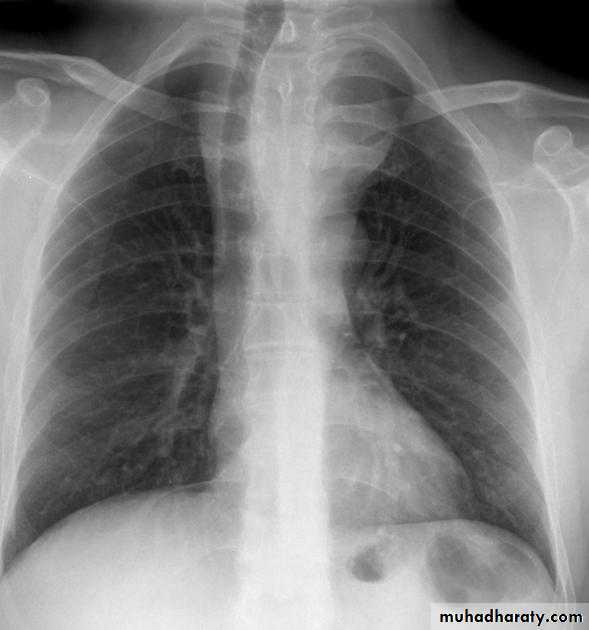

Normal thymus gland ( sail shape sign )